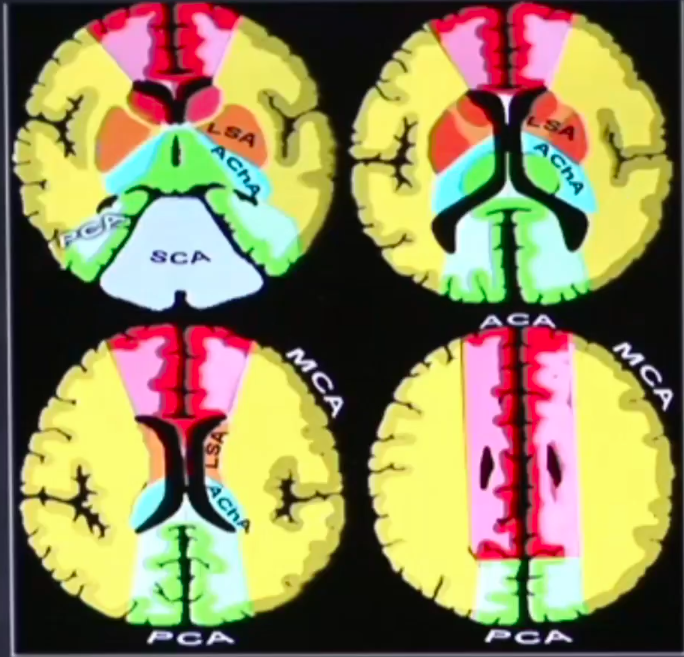

Qual a área de irrigação de cada a. cerebral?

Qual a área de irrigação de cada a. cerebral (na tomo)?